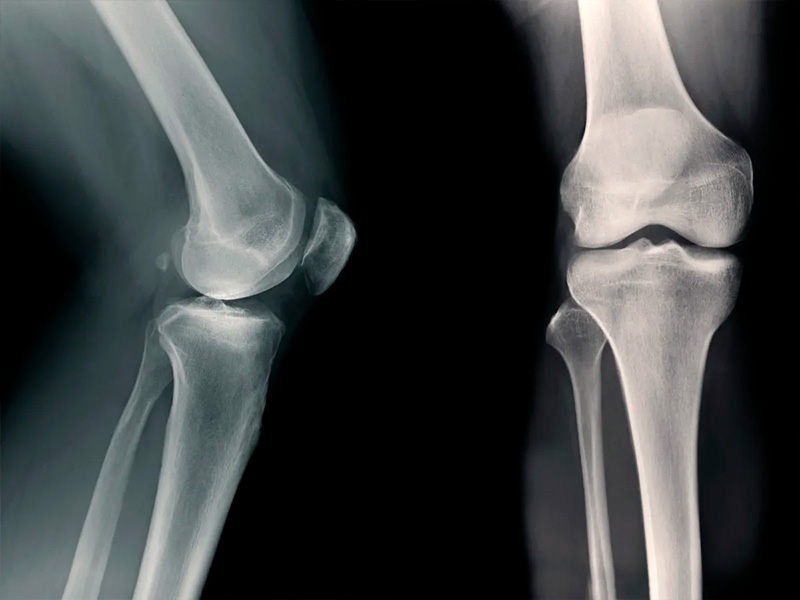

Osteoarthritis has long been perceived as an inevitable consequence of age or joint wear and tear. Today, this view is changing: increasing attention is being paid to the biochemical processes inside cartilage tissue and how they can be influenced. It is in this context that AOD 9604 is being mentioned more and more often — a peptide that was originally studied in a completely different field but unexpectedly showed interesting effects for joints.

AOD-9604 is a fragment of growth hormone that lacks its systemic action. Because of this, it is considered a safer molecule for targeted effects on tissues. In experimental models, researchers became interested in its ability to influence inflammatory reactions and cartilage metabolism. This is not about restoring a joint “at the snap of a finger,” but about influencing the environment in which degeneration develops. That is why AOD-9604 has come into focus in laboratory and preclinical studies.

When studies discuss what AOD-9604 is used for, the emphasis is almost always on its effect on cellular metabolism within joint tissues. Peptide AOD 9604 is viewed as a signaling molecule that intervenes not in symptoms, but in the biochemical processes accompanying cartilage degeneration. Experimental data show that the peptide can reduce the activity of pro-inflammatory mediators that accelerate the destruction of articular cartilage. At the same time, it affects the metabolism of chondrocytes — the cells responsible for maintaining the structure and elasticity of cartilage tissue. As a result, a more stable balance is formed between processes of breakdown and renewal. Particular attention should be paid to the effect of Peptide AOD 9604 on signaling pathways associated with cartilage matrix degradation. In osteoarthritis models, a decrease in the activity of enzymes that break down collagen and proteoglycans has been observed. This is critical, since accelerated matrix degradation underlies disease progression. In osteoarthritis, inflammation and destruction reinforce each other, forming a vicious cycle of pain, stiffness, and limited mobility. The potential value of AOD-9604 lies in the fact that it affects several links in this process at once, without stimulating aggressive tissue growth and without interfering with hormonal regulation. It is precisely this mechanism that is now considered one of the promising directions in the study of joint degeneration.